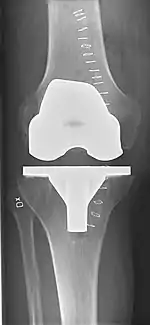

Knee replacement is routinely evaluated by X-ray, including the following measures:

- FFC: frontal femoral component angle. It is typically regarded as optimal when being 2–7° in valgus.[61]

- FTC: frontal tibial component angle, which is regarded as optimal when being at a right angle. A varus position of more than 3° has generally been found to increase the failure rate of the prosthesis.[61]

- Anterior femoral notching (the femoral component causing reduced thickness of the distal femur anteriorly), seems to cause an increased risk of fractures when exceeding about 3 mm.[62]

- LTC: lateral (or sagittal) tibial component angle, which is ideally positioned so that the tibia is 0–7° flexed compared to at a right angle with the tibial plate.[61]